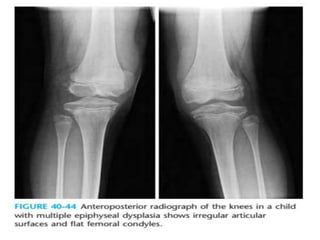

• Femoral condyles are flattened

• Double-layered patella in the lateral view

• hatchet head of humerus

Multiple epiphyseal dysplasia. Radiographs of the hip (A), left knee

(B,C), left foot and ankle (D,E), and left wrist (F) show lack of epiphyseal

ossification centers with punctate calcifications in the knee.

Multiple epiphyseal dysplasia in an adolescent. AP and lateral radiographs of

the knee (A,B) and ankle (C,D) showing irregular epiphysis with joint deformities.